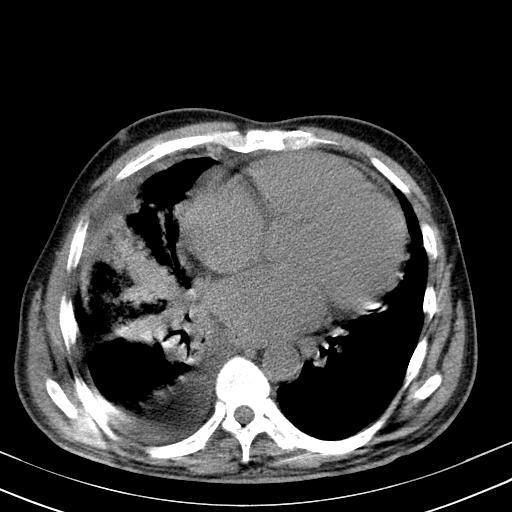

以下是引用zxl51642在2010-3-21 17:06:00的发言:[br]右下中心型肺癌并阻塞性肺炎/不张,纵膈淋巴结肿大,右侧大量胸腔积液,左侧少量胸腔积液,少量腹水。建议纤维支气管镜进一步检查。